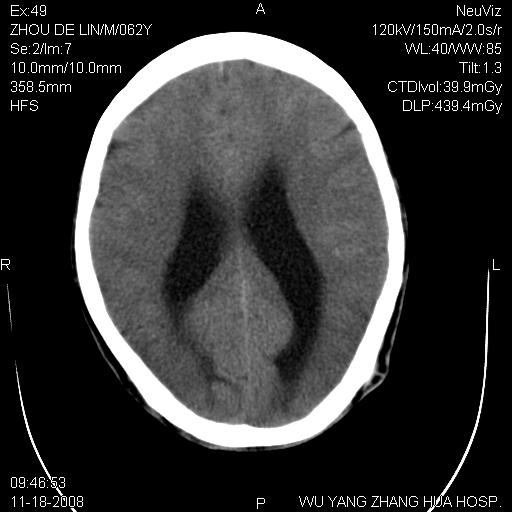

患者近段时间偶有头晕,无其他不适。既往有糖尿病病史。

小脑中线区见一类圆形混杂密度影,四脑室受压变形,其后方见一边界清楚的囊性低密度影,幕上脑室扩张。小脑中线区肿瘤,儿童多见于髓母细胞瘤,成人多见于胶质瘤。

诊断:小脑胶质瘤可能性大。建议增强扫描

小脑囊实性占位病变、脑室系统积水扩张、脑肿胀。

小脑囊实性占位病变、脑室系统积水扩张,建议增强

诊断:小脑胶质瘤可能性大。建议增强扫描。支持!

1)小脑蚓部(偏左侧)占位性病变;不排除转移瘤可能。建议行进一步检查。2)脑积水。